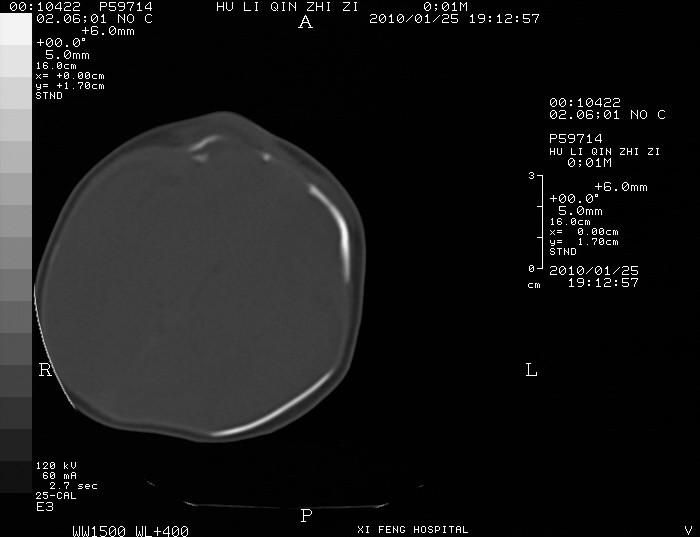

男  新生儿,曾做b超股骨长5.5厘米,疑畸形,家族中有多个身才矮小.曾孕两次,一次流产,一次宫内死亡

谢谢,我也考虑,颅骨有问题吗?仅仅是颅缝增宽还是还有骨化差。

如果颅骨有骨化差,那就不应该考虑软骨发育不全了,

四肢干骺端呈喇叭口型缺损,颅骨缝增宽,支持软骨发育不全。